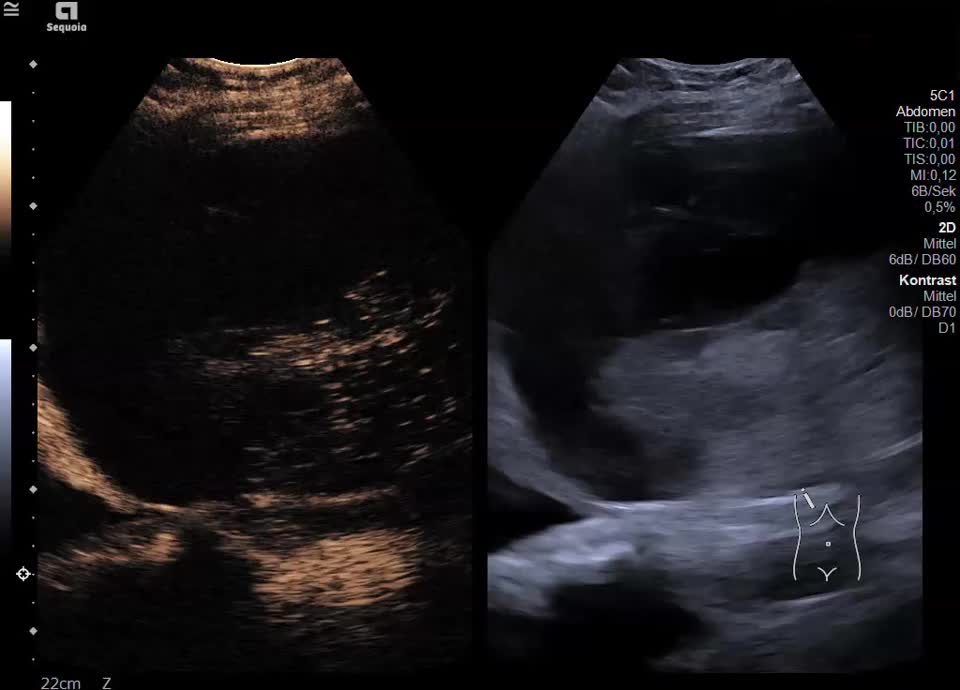

Leberhämatom (HELLP-Syndrom)

Kasuistik: die 48-jährige Patientin hat während ihrer Schwangerschaft ein HELLP-Syndrom entwickelt. Zustand nach Sectio bei schwerer Präeklampsie und Gemini in der 37. SSW. Post-partales HELLP mit Leberhämatom und beginnendem Leber- und Nierenversagen. Durch die Interventionelle Radiologie erfolgte die CT-gestütze Embolisation mit Coils. Sonographisch stellt sich jetzt ein 12x13cm messendes subkapsuläres Hämatom im rechten Leperlappen mit Anzeichen einer beginnenden Organisation dar. Die Läsion nimmt kein Kontrastmittel auf, eine aktive Blutung kann ausgeschlosen werden.